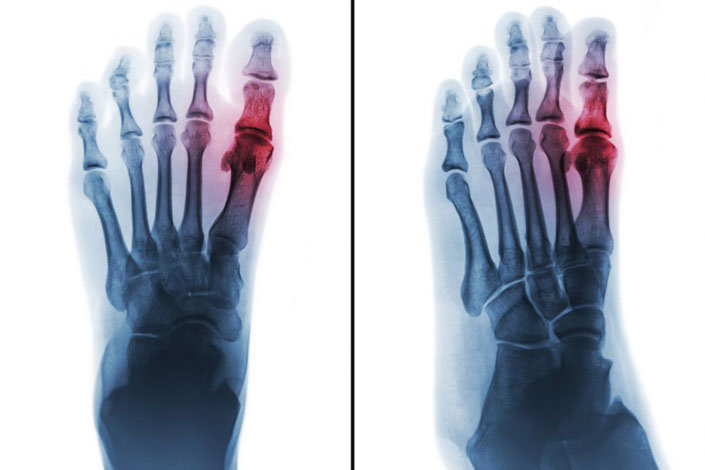

Leczenie bólu u pacjenta z ostrym napadem dny moczanowej

Summary: Acute gouty arthritis is the most common form of arthritis that requires urgent pharmacological treatment. The recommended drugs of first choice in a gout attack are colchicine, non-steroidal anti-inflammatory drugs and glucocorticosteroids. The article presents the rules of treatment based on the current recommendations and results of clinical trials. The latest therapeutic options with interleukin 1 (IL-1) inhibitors are also included. In each case, it is extremely important to select the drug individually for a specifi c patient. The presence of comorbidities, contraindications, the possibility of drug interactions, duration of the attack and the severity of symptoms should be taken into account.

Dna moczanowa jest chorobą metaboliczną wynikającą z odkładania się kryształów moczanu sodu, powodującą zarówno ostre napady zapalenia stawów i kaletek maziowych, jak również przewlekłe zapalenie stawów. Występuje u osób z hiperurykemią – podwyższonym stężeniem kwasu moczowego w surowicy, którego norma dla kobiet wynosi ok. 6 mg/dl, a dla mężczyzn ok. 6,8 mg/dl. Częstość występowania dny moczanowej stale się zwiększa; obecnie w Europie jest określana na poziomie 0,9–2,5% (1), a w USA – na 3,9% (2), wraz z narastającą epidemią otyłości i związanych z nią zaburzeń metabolicznych.